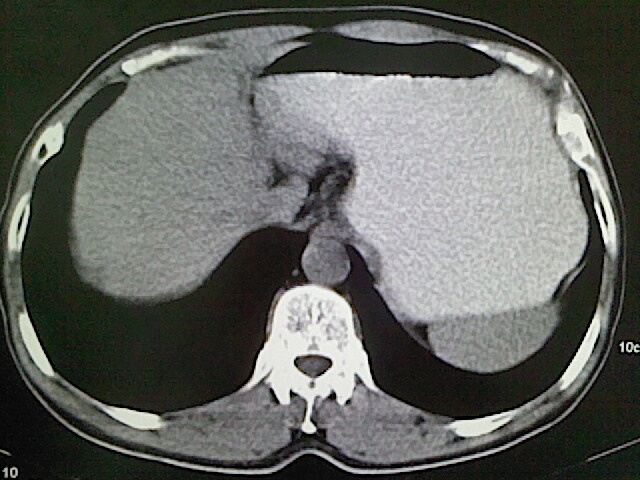

标题: CT18630:男,54岁,乙肝,大家看怎么样? [打印本页]

男,54岁,乙肝,大家看怎么样?

肝脏的要有增强敢说话

未见明确异常;建议必要时行ct增强扫描检查。